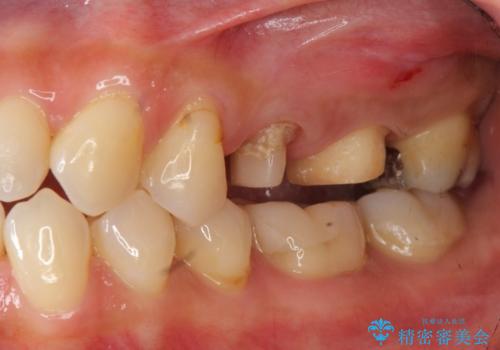

放置し崩壊した歯 セラミック治療による咬合機能回復

- 忙しくて歯科医院に通えず、ついに歯が折れてしまい治療を希望され来院されました。

虫歯を丁寧に除去したのち、なんとか歯を残せる見通しがたったので根管治療を行いセラミック補綴を行いました。